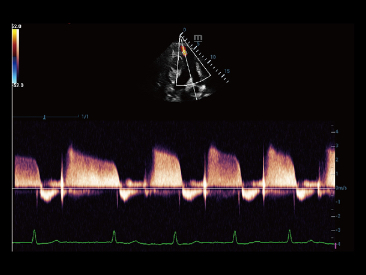

Mindray? ??? ??? ?? ??? ???? ??? ?? ??? ??? ????? ??? ????. ?? ???? ZONE Sonography? ??? ???? ?? Resona 7? ??? ZST+ ???? ?? ?? ? ?? ??? ????? ?? ??? ??? ??? ? ?? ????.

?? Resona 7? ???? ??? ?? ???? ??? ??? ???? ??? ?? ???? V Flow? ?? CNS ??? ?? 3D ??? ???? ?? ???? ?? ??? ?? ?? ?? ??? ??????. ???? ??? ??? ?? ?? ??? ??? ?? ?? ??? ??? Resona 7? ??? ???? ???? ??? ??? ??? ????.